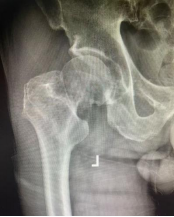

术后复查的 X 线片显示,两位老人髋关节置换位置均非常理想,为后续康复锻炼提供了必要条件。在医护团队的精心指导和鼓励下,两位老人术后第三天便成功下地站立、行走。